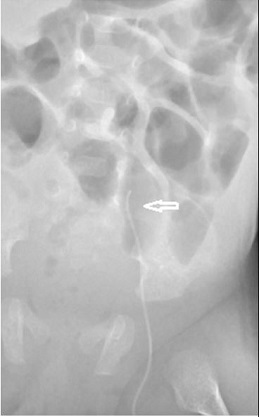

This lateral x-ray shows a PICC line in the left lumbar vein taking a posteriorly deviated route (arrows). The correct route would show the line continuing to lie anterior to the spine. | |